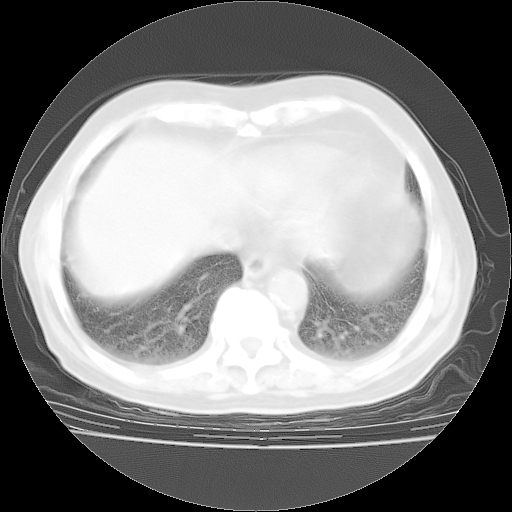

4月28日肺部CT——再次出现类似去年5月9日——透光度降低,“间质性”改变。

4月28日肺部CT